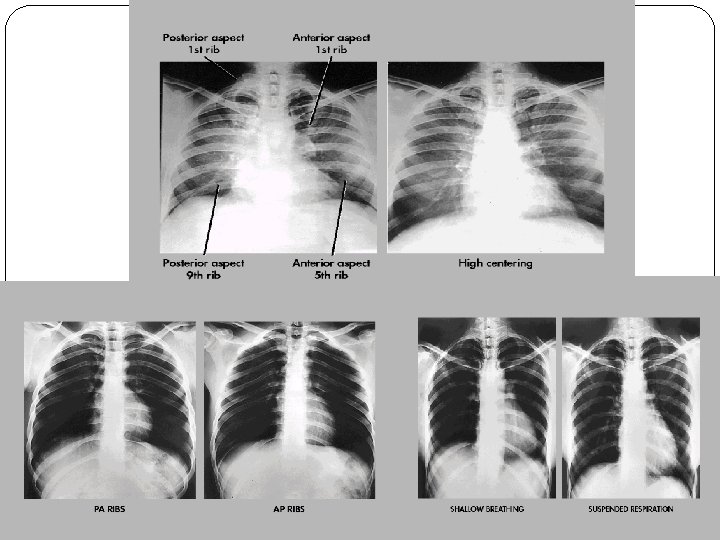

PA anterior ribs (upper ribs) (Basic) Film Size: 14 x 17 in. (35 x 43 cm). Crosswise or lengthwise * SHIELDING: Shield gonadal region. Patient Position: For upper ribs: Patient erect (preferred), or prone if necessary , with arms down to the side. Part Position: shoulders rotated anteriorly to remove scapula away from the lung fields. No rotation of thorax or pelvis. k. V (65 – 75 for above diaphragm. Distance: 100 cm or 40 in, grid. CR: perpendicular to film. CP: To T 7 (7 to 8 in or 18 to 20 cm below vertebra prominens as for PA chest) Collimation: collimate on four sides to area of interest. NB/ suspend respiration on inspiration.

Structure shown: ribs 1 - 9 or 10 visualized above diaphragm